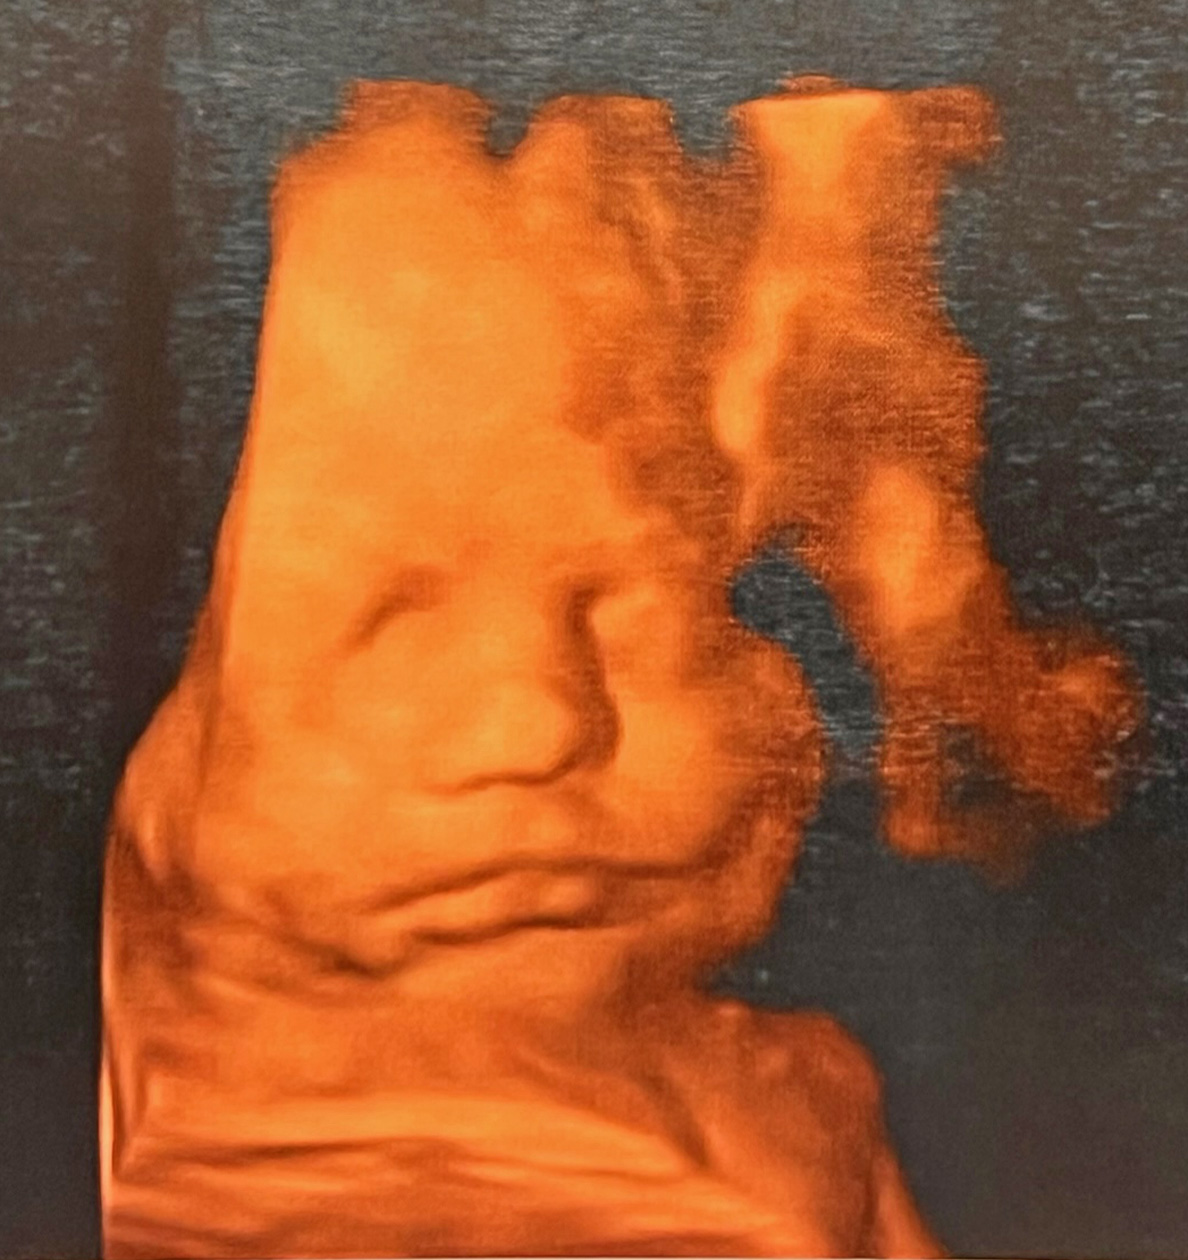

though we had seen you only in

fuzzy black and white scans, your

little face mooshed up inside your

mama, whose voice you already knew,

Henry in utero at 30 weeks,

son of Lauren Just Giel and Gerald Giel